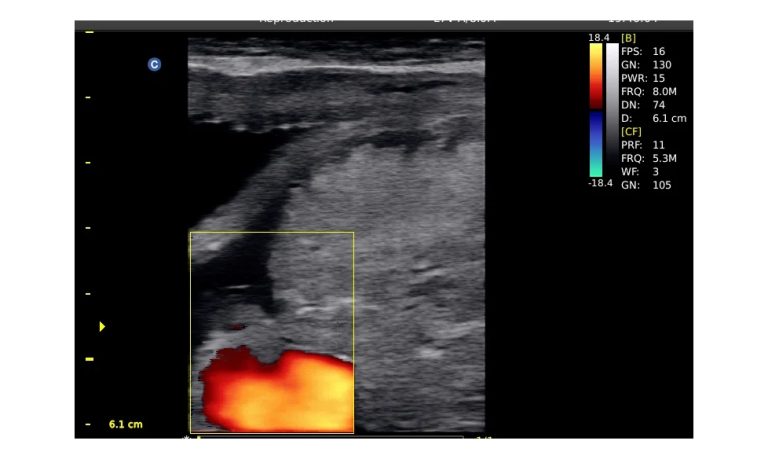

Ultrasound

Wide range of Ultrasound machines that suites a variety of applications from abdominal to rectal scans, we take in consideration how the world is moving towards mobility and mobile applications.

SonoScape Pro Pet E11

Smart Imaging

Introducing the first portable ultrasound with the C-Field+TM platform, redefining diagnostic imaging. Designed for veterinarians, it delivers unmatched clarity, ultra-fast processing, and seamless adaptability for all species. Experience Smart Imaging, Heartfelt Care—anywhere.

Equipped with cutting-edge veterinary software and optimized workflows, it embodies our commitment to Smart Imaging, Heartfelt Care – Wherever Their Journey Leads, with unparalleled performance and adaptability, this innovative system empowers veterinarians to provide exceptional care across all diagnostic applications,

Esaote MyLab Sigma; So Fast, So Easy

Esaote’s new MyLab™SigmaVET is the smart, portable solution that allows use of an ultrasound whenever a quick and complete diagnosis is required.

EBIT50/60 VET

All the power you need

The EBit provides all the power you need for today´s challenging clinical environment, yet remain ultra-portable, ultra-affordable. With its cutting-edge imaging technologies, precise and intuitive workflow, ergonomic and eco-friendly design, versatile transducers for all applications from top to toe, we firmly believe the EBit to be the very best portable ultrasound in its class today.

ECO5 VET

Ultra-Portable, Ultra- Affordable, Color doppler

The multi-purpose user presets, comprehensive measurement & report system, built-in EasyView image achieve system, quick image storage / retrieve / transfer, one-button direct print, make the complete workflow better than what you can dream of.